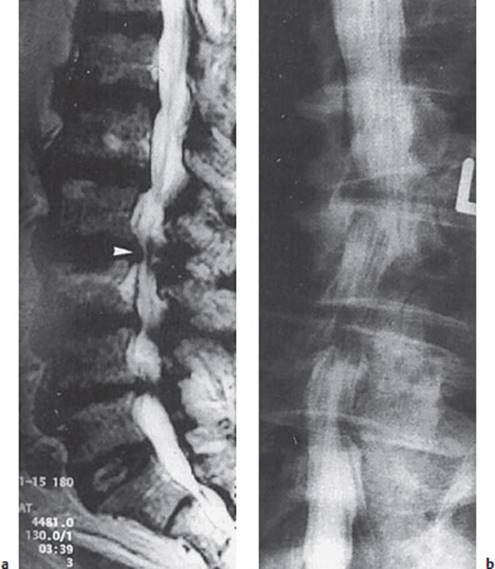

Fig. 12.7 Left S1 radicular compression in a 40-year-old man. Myelography (a) reveals a broadened and shortened left S1 nerve root (arrowhead) and an indentation of the dural sack from the right at this level. CT (b) reveals high-grade spondyloarthrosis and bilateral stenosis of the lateral recesses.